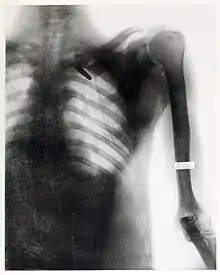

Radiograph by Elizabeth Fleischman of the chest of Private James Edwards, showing a bullet lodged near the spine.

In December 1898, she began to provide services as a radiographer to the United States Army, who had been sending wounded soldiers from the Spanish-American War's Pacific theater back to the United States through San Francisco.[14]

She received praise for her work during the Spanish-American War from the Surgeon General of the Army George Miller Sternberg.[19] Several of her radiographs were also used by William C. Borden to illustrate his book on the medical use of X-rays in the Spanish-American War.[15]